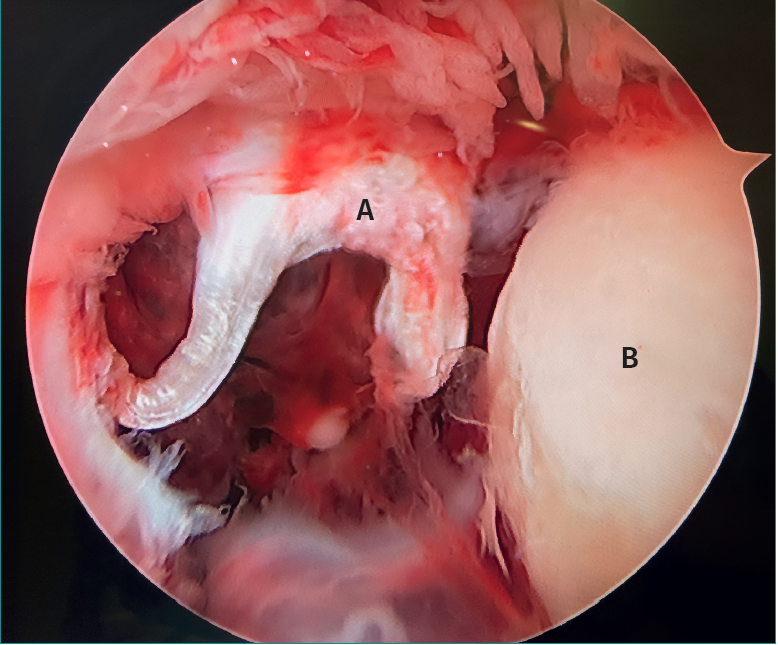

La letra pi en el tobillo

- La letra pi en el tobillo